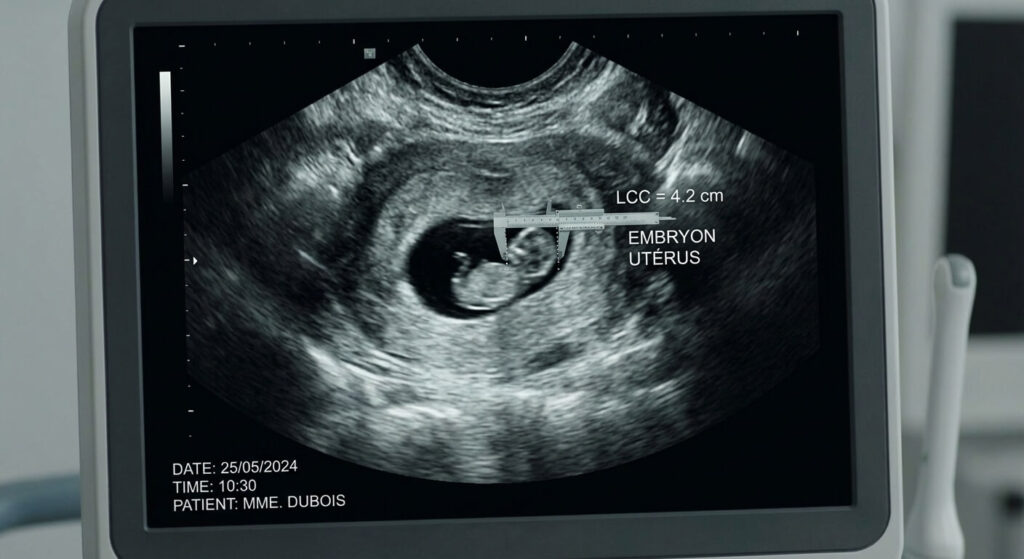

- 📏 La mesure de référence : L’échographiste calcule la Longueur Crânio-Caudale (LCC), de la tête aux fesses de l’embryon, pour dater précisément l’âge gestationnel au jour près.

Le fait d’avoir visualisé et mesuré une activité cardiaque embryonnaire change drastiquement la grille de lecture du médecin. L’activité cardiaque est généralement détectable par échographie endovaginale lorsque l’embryon (la LCC) atteint la taille de 5 millimètres.

« La pire chose qu’une patiente puisse faire en sortant de mon cabinet, c’est de comparer la taille de son embryon sur les forums internet. En début de grossesse, un millimètre de différence sur l’écran correspond à un jour entier de développement. C’est de l’horlogerie fine. Mon rôle n’est pas de juger la taille en fonction du jour où la patiente pense avoir conçu, car l’ovulation est secrète. Mon rôle est de m’assurer que la taille du sac, la taille de l’embryon et la présence du cœur sont cohérentes entre elles. Si un embryon de 4 mm possède une belle vésicule vitelline et un cœur tonique, c’est le tableau parfait d’une grossesse de 6 semaines. Je leur donne rendez-vous 10 jours plus tard : si l’embryon a grandi d’environ 1 millimètre par jour, le pari est gagné. »